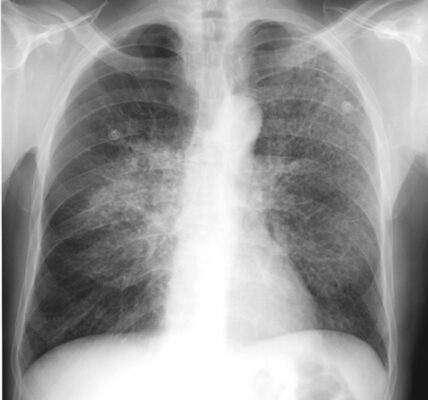

- Điển hình biểu hiện là một viêm phổi kẽ dạng lưới, quanh rốn phổi hoặc như một bệnh khoảng chứa khí có thể trông giống như dạng phân bố trung tâm của phù phổi (Hình 5).

- Các biểu hiện khác, chẳng hạn như bệnh khoảng chứa khí một bên hoặc bệnh khoảng chứa khí loang lổ ít phổ biến hơn.

- Thường không có tràn dịch màng phổi và không có hạch rốn phổi